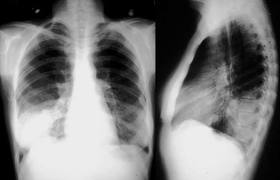

La evidencia disponible para la neumonía adquirida en la comunidad (NAC),y exacerbación aguda de enfermedad pulmonar obstructiva crónica (EAEPOC), fuera de la UCI respalda un tratamiento de corta duración de 5 días en pacientes que han mejorado clínicamente. Los esfuerzos de la comunidad científica deben dirigirse a implementar esta evidencia en la práctica diaria. Se necesitan ensayos controlados aleatorios de alta calidad para respaldar duraciones de tratamiento aún más cortas para la NAC y la EAEPOC, para establecer la duración óptima del tratamiento de la neumonía adquirida en el hospital y la sinusitis aguda, y para evaluar una duración más corta utilizando un esquema de dosificación óptimo de penicilina en pacientes con faringoamigdalitis. Lancet Infect Dis.   4 de septiembre de 2024